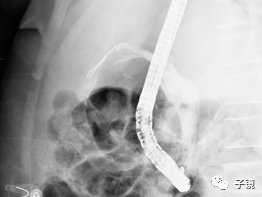

操作快两小时了,镜子固定困难,太易滑镜,留置鼻胆管,结束战斗。

后记:术后患者无不适,术后第五天行鼻胆管造影,未见结石残留,造影剂排泄通畅,拔除鼻胆管后出院。